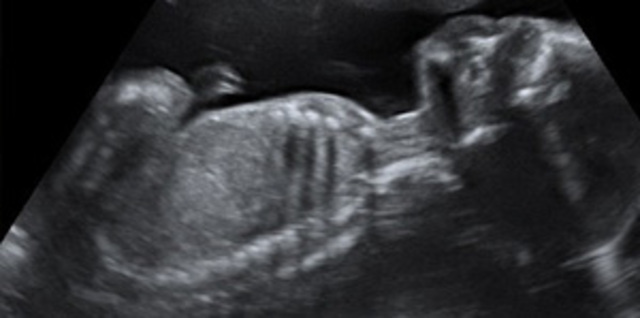

• SEMANA 32

SEMANA 32

El bebé pesa 1.800 gramos y mide unos 42 centímetros de pies a cabeza en la semana 32 de embarazo.

Todavía el diámetro de la cabeza sigue siendo mayor que el del abdomen, pero el aspecto del feto ya se parece bastante al de un recién nacido.

Los pulmones aún no están maduros, debido a que no tienen surfactante pulmonar (una sustancia que hace que los alveolos pulmonares no se colapsen y se mantengan abiertos).